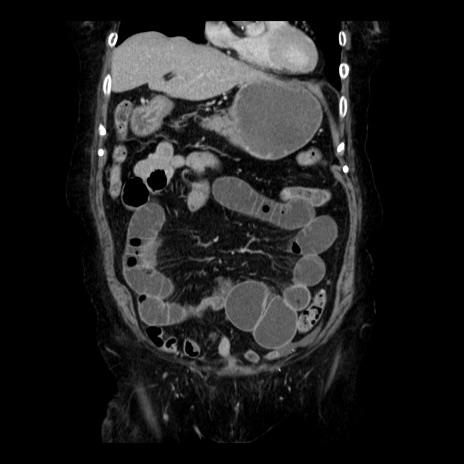

症例14(冠状断像)

【症例】 90歳代女性

【主訴】 腹痛・嘔吐

【現病歴】今朝から左側腹部痛を認めた。 経過観察していたが、嘔吐を認めたため来院。

【既往歴】 子宮癌術後

【身体所見】 意識清明、BP 127/54mmHg、P 98bpm Sp02 95%(RA)、BT 35.8°C、腹部平坦・軟腸ぜん動音聴取良好、右下腹部圧痛(+) 反跳痛なし

【データ】WBC 9800、CRP 0.46